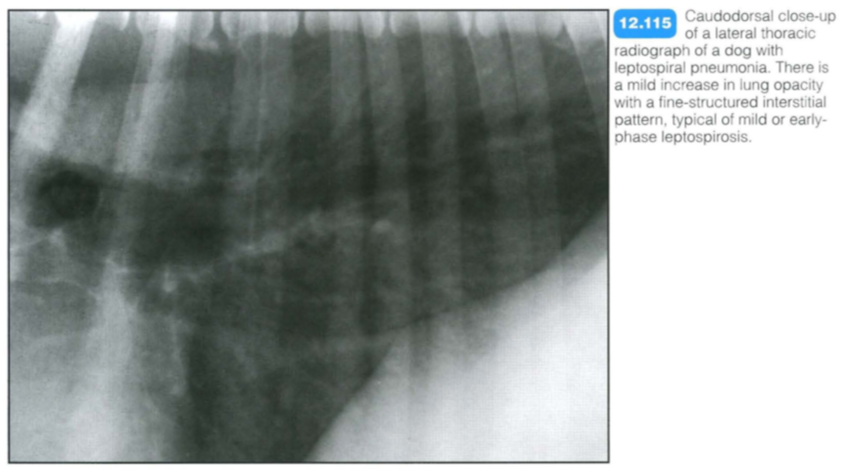

Canine leptospiral pneumonia

Clinical signs relate to acute renal failure rather than pulmonary involvement.

Radiography: